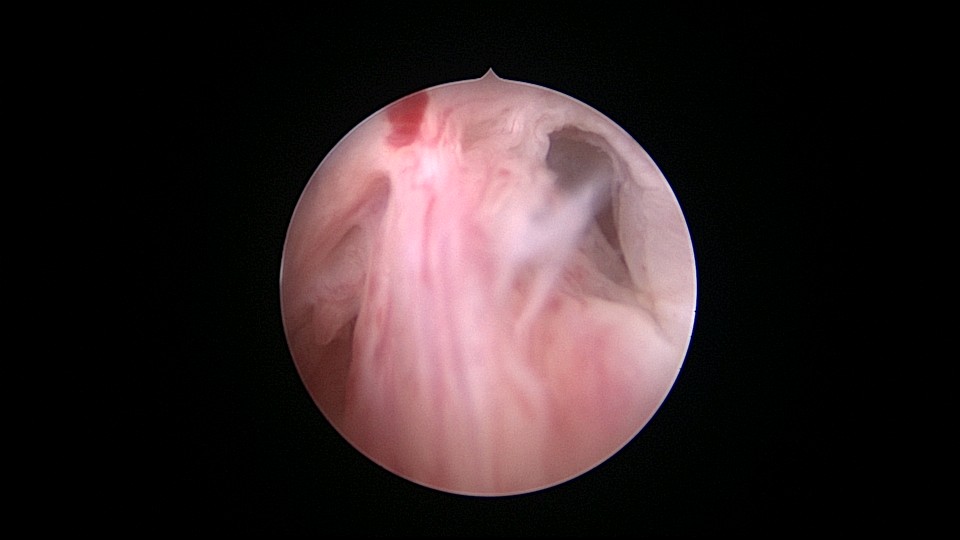

患者55岁,G1P1,顺产1次。安环31年,绝经3年,妇科检查发现宫颈外口息肉,B超宫腔未见分离暗区。子宫前位,宫腔镜见宫颈管下段多发息肉,宫颈内口粘连,宫腔少许淡黄色脓液流出,宫型环位置正常,被镜鞘推挤变形。助手单极电针切除宫颈管息肉时进针过深,引起较多出血,视野不清楚,接手手术,先止血、切除息肉,然后异物钳取出节育环,宫腔无其他异常。病检为宫颈管息肉。